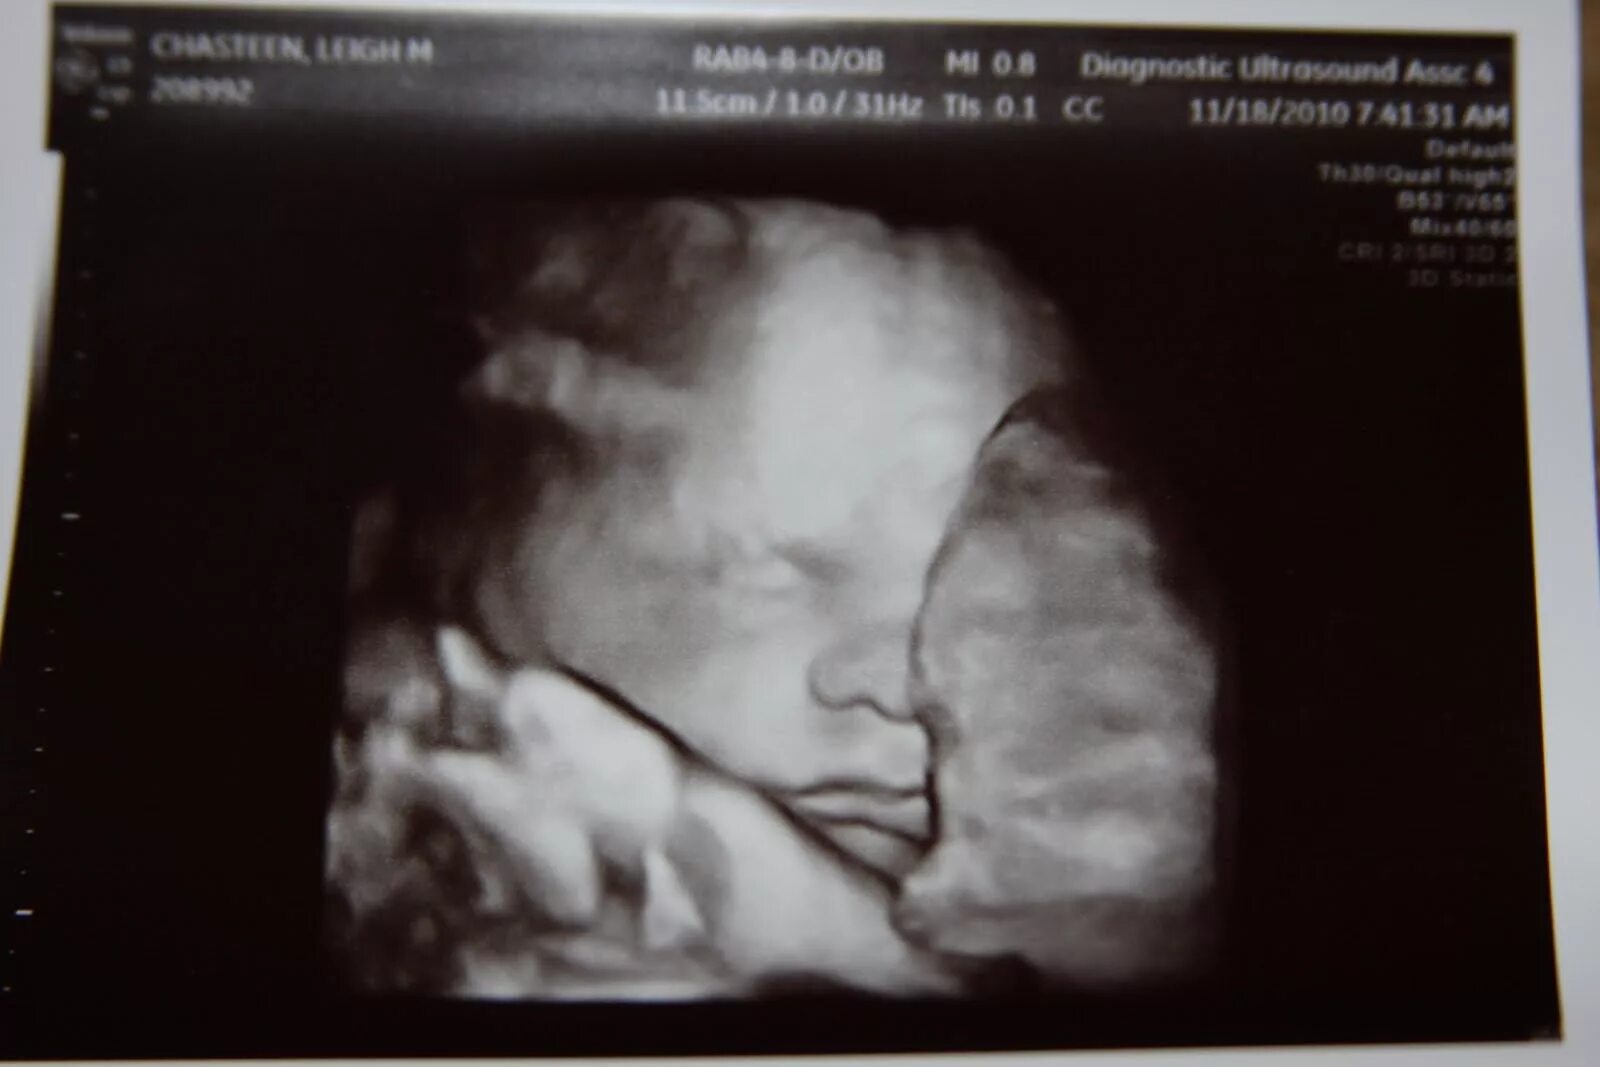

Развития плода 30 недель